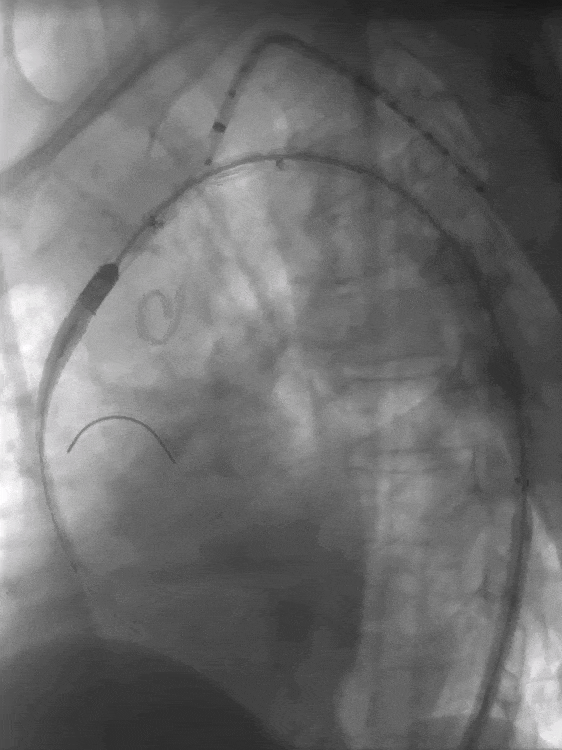

3. 经左肱动脉鞘管引入单弯导管,头端正对于主动脉弓处覆膜支架,置入250T导丝并配合单弯导管,顺利在左锁骨下动脉根部处原位开窗,手推造影明确导丝已进入覆膜支架。

送入单弯导管及250T导丝

250T导丝成功于LSA根部破膜

4. 依次使用3-30mm球囊、8-40mm球囊扩张开窗口;并通过球囊带鞘技术通过主动脉开窗部位。

3-30mm球囊扩张

8-40mm球囊扩张

RAO确认

球囊带鞘进膜